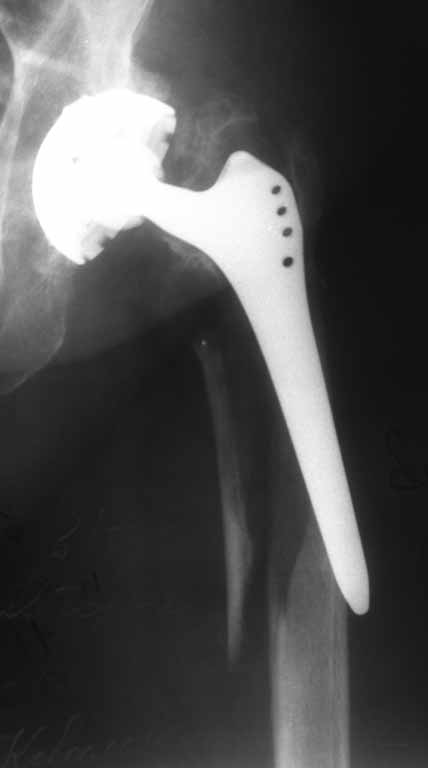

Пациентка 86 лет. Травма в результате падения.планируется замена ножки на ревизионную +

серкляжи на отломки. Может что нибудь еще?